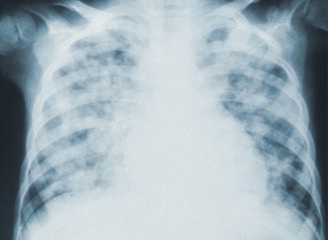

Pulmonology Consultations

Advanced Diagnostics

In today's medical landscape, the utilization of state-of-the-art technology has revolutionized the diagnosis and management of pulmonary diseases. Advanced imaging techniques, alongside innovative diagnostic tools, enable healthcare professionals to identify respiratory conditions with remarkable accuracy. This enhanced capability allows for timely interventions, significantly improving patient outcomes. Furthermore, the integration of artificial intelligence in monitoring respiratory health facilitates personalized treatment plans tailored to individual needs.